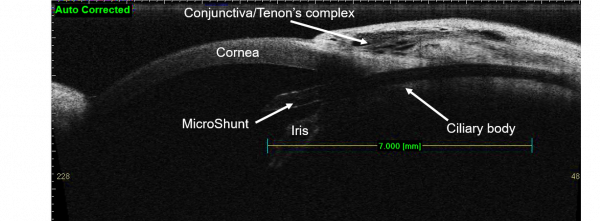

The device has a total length of 8.5 mm, which is divided by a 1mm “fin” into distal (3 mm) and proximal (4.5 mm) segments. The external lumen is 350um and the internal lumen is 70um with a beveled tip at the proximal end.

The design of the device obeys assumptions of the Hagen-Poiseuille equation for the prediction of pressure. Therefore, providing that aqueous production is > 2uL/min, postoperative IOP should be maintained above 5 mmHg. When positioned properly, the distal end of the MicroShunt should filter aqueous to the subconjunctival and sub-Tenon space 6 mm posterior to the limbus, allowing for posteriorly directed flow and bleb formation.

The device may be implanted under topical, local, or general anesthesia. After informed consent and standard ophthalmic prepping and ocular exposure, a 3 to 4 clock-hour fornix-based conjunctival peritomy is created – typically in the superonasal or superotemporal quadrants. Care should be taken to disinsert Tenon capsule attachments at the limbus and wide, blunt dissection should be carried out under this layer of tissue. Hemostasis may be performed as necessary using standard methods. Mitomycin-C soaked sponges are then applied to the scleral bed. Mitomycin-C concentration and duration of applications are left to the surgeon’s discretion based on judgment of risk for postoperative fibrosis. After removal of the sponges, the scleral bed is rinsed with balanced salt solution. The sclera is then marked 3 mm posterior the limbus. A scleral tunnel is initiated at this point along the curvature of the globe, followed by change trajectory at the level of the trabecular meshwork before entering the anterior chamber parallel to the iris plane. Different techniques and tools may be used to perform this portion of the procedure. The device is then inserted through this tract using non-toothed forceps, with care to maintain the proximal tip in a bevel-up position. The device is advanced until the fins are just tucked within the distal end of the scleral tunnel. In this position, 2 to 3 mm of the proximal end of the device should extend into the mid-anterior chamber and parallel to iris plane.

When properly positioned and unobstructed, aqueous flow should be visible at the distal end of the device. If no flow is visible and an obvious proximal obstruction is not visualized, the distal end may be “primed” using an anterior chamber cannula and balanced salt solution. A corneal paracentesis may be created at surgeon discretion for additional control of the anterior chamber or to test device patency via injection of balanced salt solution. Once the device has been placed and flow has been verified, conjunctiva and Tenon capsule are repositioned over the device, taking care to avoid distal obstruction of implant. The distal end of the implant should lie flush with the sclera and a second instrument may be used to direct it in this manner. The conjunctiva and Tenon capsule are then closed using the surgeon’s preferred technique. A fluorescein strip is used to confirm adequate wound closure and the eye is protected according to the surgeon’s usual protocol. There is also a description of the device's implantation through the ciliary sulcus, a potemtial surgical solution for patients at high risk of corneal decompensation [1]